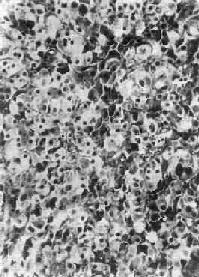

图15-16 肾上腺皮质腺瘤 上图 下图 (二)肾上腺皮质癌 肾上腺皮质癌(adrenocortical carcinoma)甚少见,一般为功能性,发现时一般比腺瘤大,重量常超过100g,呈浸润性生长,正常肾上腺组织破坏或被淹没,向外侵犯周围脂肪组织甚至该侧肾。小的腺癌可有包膜。切面棕黄色,常见出血、坏死及囊性变。镜下分化差者异型性高,瘤细胞大小不等,并可见怪形核及多核,核分裂像多见(图15-17)。常转移到腹主动脉淋巴结或血行转移到肺、肝等处。分化高者镜下像腺瘤,如果癌体小又有包膜,很难与腺瘤区别,有人认为直径超过3cm者,应多考虑为高分化腺癌。

图15-17 肾上腺皮质癌 (三)肾上腺髓质肿瘤 肾上腺髓质来自神经嵴,原始细胞为交感神经母细胞,以后分化为神经节细胞及嗜铬细胞,因此可形成神经母细胞瘤、神经节细胞瘤及嗜铬细胞瘤(神经母细胞瘤及神经节细胞瘤详见第十六章)。 嗜铬细胞瘤(phenochromocytoma) 80%~90%发生于肾上腺髓质,绝大部分为单侧单发性,偶尔见于双侧,90%为良性,好发于30~50岁。肿瘤细胞可分泌去甲肾上腺素和肾上腺素,以去甲肾上腺素为主,偶尔也分泌多巴胺及其他激素,故临床主要有儿茶酚胺过高的症状,表现为血压增高,多呈间歇性发作,并伴有头痛、发汗、末梢血管收缩、脉搏加快、血糖增高、基础代谢上升等症状。肉眼观,大小不一,平均100g左右,甚至可达2000g,有包膜,切面灰红色、灰褐色,常见出血、坏死、囊性变及坏死灶。镜下嗜铬细胞为大多角形细胞,形成细胞索或细胞巢,可有不同程度的多形性,有时出现巨细胞,瘤细胞胞浆内有大量嗜铬的微细颗粒;电镜下,颗粒有包膜,电子致密度低者含有肾上腺素,而包膜不清楚电子致密度高者含有去甲肾上腺素,用免疫组化方法亦可显示。间质主要是血窦。良、恶性肿瘤在细胞形态方面无截然界限,包膜被侵犯並不能作为恶性的肯定证据,但如有周围组织浸润及转移,则属恶性无疑。 肾上腺外嗜铬细胞瘤多为多发性,位于主动脉两侧副节细胞分布处,常称为副节细胞瘤(paraganglioma)。本瘤好发于10~20岁,多数为多发性内分泌肿瘤的一部分,40%为恶性。